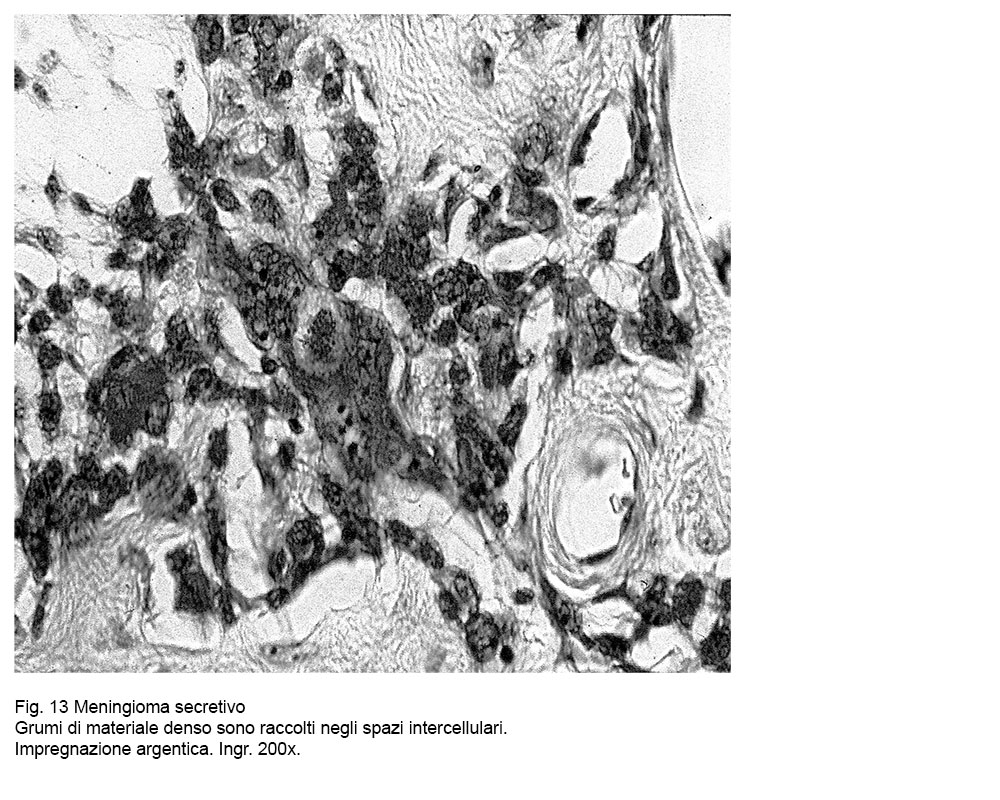

Fig.11

Le cellule meningiomatose con aspetto sferoidale-globoso con accresciuta volumetria esercitano frequentemente su i piccoli vasi intratumorali una pressione ab-estrinseco su le pareti, provocandone il collabimento. Negli ambiti dello stroma, mediante il metodo della impregnazione argentica si repertano grumi di materiale amorfo argentofilo che impregna fibrille connettivali, oppure inibiscono le pareti dei vasi e i tessuti lassi perivascolari; in altri campi microscopici lo stroma appare occupata da materiale amorfo, da materiale granuloso o da grumi di materiale denso ed omogeneo.

Fig.13